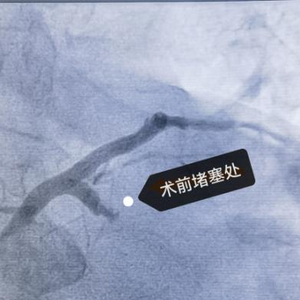

术前造影,回旋支血管开口处完全闭塞

在与患者及家属进行充分沟通后,医院的胸痛中心紧急启动了导管室(介入诊疗科)。心血管内科副主任医师张登洪在凌晨两点紧急赶到医院,而介入诊疗科的工作人员也迅速做好急诊手术的准备。

支架植入后血管通畅、血流恢复

在介入诊疗科和心血管内科的密切协作下,医疗团队紧急为患者进行了血栓抽吸和支架植入手术。随着一枚支架被植入体内,患者手术后血流恢复正常,手术成功。